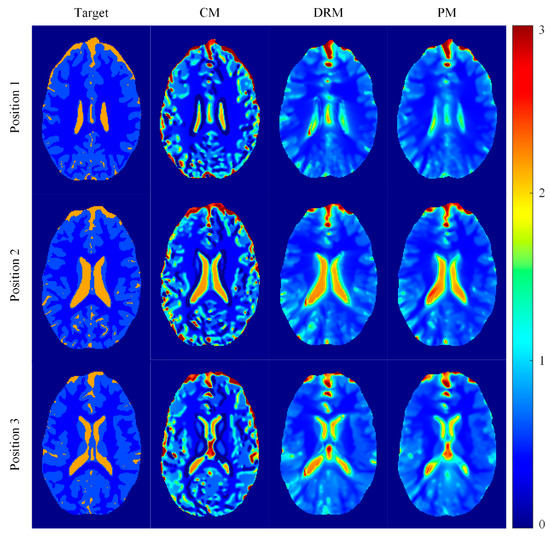

4.3. Experimental Results